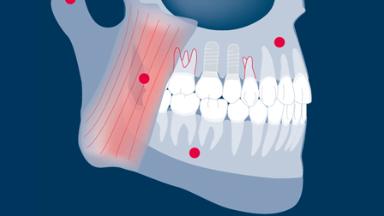

- recognize characteristics of occlusal forces and biophysical differences in how teeth and implants respond to them

- discuss the potential impact of occlusal forces on complications and failures of implants and their prostheses

- apply recommended guidelines for occlusal management in implant therapy